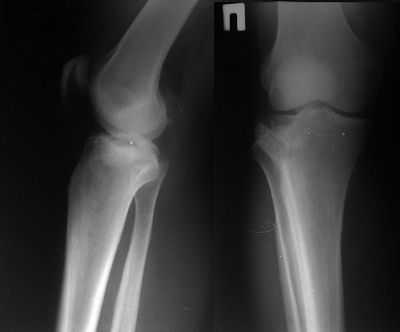

Denosumab является предназначенной терапией, чтобы предотвратить потерю костной массы. Это останавливает прогрессивную деструкцию кости и распространение опухоли в некоторых пациентах с неоперабельной гигантоклеточной опухолью (GCT) кости. Статья издала Онлайн Сначала при Онкологии Скальпеля, сообщает, что это могло изменить стандартную практику лечения. …